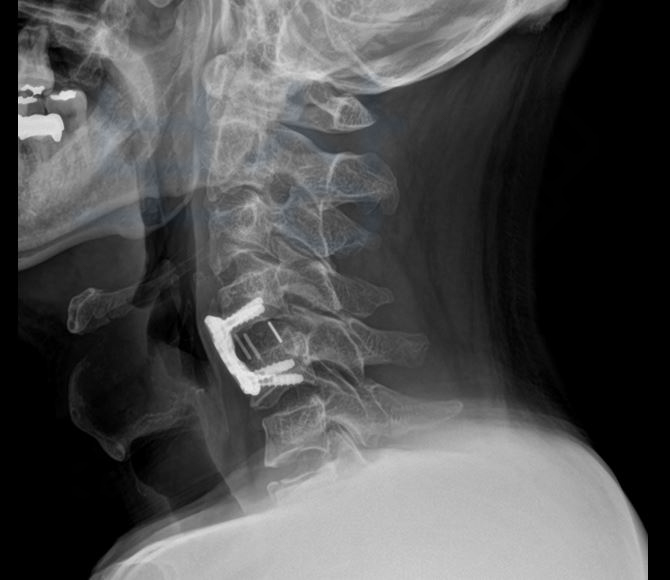

경추4번 ~ 5번 탈구 및 경추7번 골절 진단을 받으셨습니다. 의뢰인의 상태는 수술하지 않을 수 없는 심각한 상황이었기 때문에 경추 골절 수술을 진행하게 되었고

경추 4번과 5번 척추체를 고정하는 즉** < 경추 전방 유합술 >** 을 진행하게 되었죠.

위 최초 요양신청 의료기관의 소견란을 보시면 전방 경추 추간판제거술 및 골유합술고 고정술 즉 경추 전방 유합술을 했다는 설명입니다. . . . 낙하물에 맞아 큰 사고를 당한 의뢰인 김@@님 의뢰인은 업무중 발생한 사고로 사고 경위가 명확했으며 3일 이상의 요양이 필요한 상황이었으므로 병원 원무과의 도움을 받아 산재 신청서를 작성 하신 후 관할 근로복지공단으로 무사히 산재 신청을 하실 수 있었습니다.